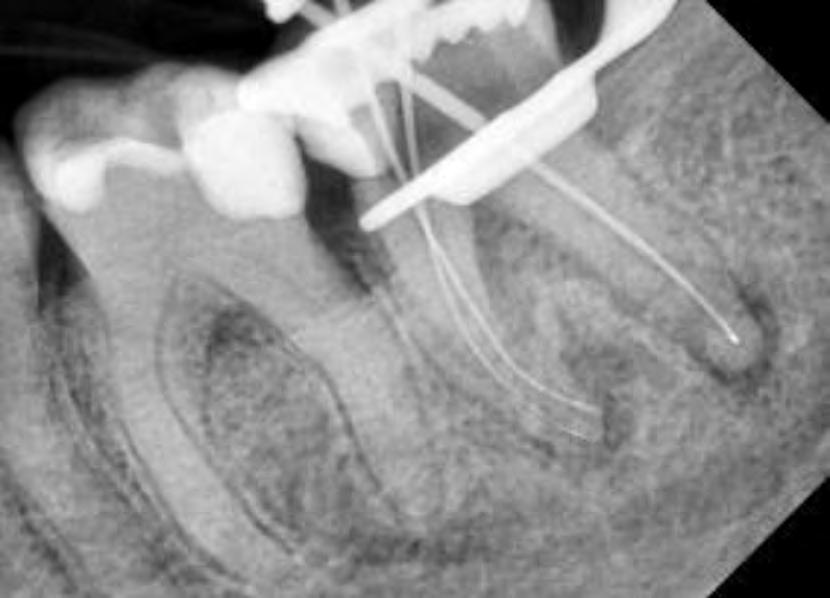

Followed shaping of coronal and middle part, WL was determined with K-File #10 and shaping procedure were completed with martensitic X7 (EdgeEndo, Albuquerque, NM) instruments in sizes 17 and 25, .04 taper. The instruments were used with a reciprocating motion (150-30) to increase resistance to both torsional and flexural stress (fig.2)

Fig.2

The root canal system was rinsed, dried and then obturated with an hydraulic single cone-technique and bioceramic sealer (BUSA, BC Sealer). Two periapical radiographs with different angulations were taken to verify treatment quality (Fig.3-4).

Clinician’s suspect of unusual anatomy of the distal root anatomy was confirmed by the angulated radiograph that showed an abrupt hidden curvature in the apical third of the canal. Nevertheless the crown-down approach (shaping the coronal and middle part first, thus reducing coronal interferences) and the Fig.3 Fig.4

proper selection of very flexible and resistance instruments, combined with a safer reciprocating clinical motions, allowed to properly negotiate the hidden curvature with no iatrogenic errors . The X7 instruments were chosen because their innovative manufacturing process which provides them with unprecedented flexibility and resistance to cyclic fatigue, allowing practitioners to perform procedures that would be difficult, if not unimaginable, with traditional non-heated files. More precisely, EdgeEndo has focused research and development in the heat-treatment of NiTi files and has developed a proprietary process to produce FireWire™ files that exhibit 2 to 8 times the resistance to cyclic fatigue (and flexibility) than other NiTi files. The benefits of a flexible file seem obvious in complex curvature, but martensitic X7 files also offer another advantage: less “shape memory”. Although shape memory may seem beneficial, it can cause a file to “bounce back” in the tooth, putting lateral pressure on the canal wall, potentially leading to canal transportation or ledging. The present case shows how the excellent clinical performance of X7 files in a very complex anatomy, by avoiding the above mentioned , common iatrogenic errors.